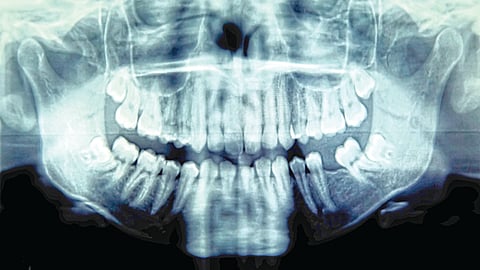

2022 च्या एका अभ्यासानुसार, ज्या 59 रुग्णांवर ही शस्त्रक्रिया करण्यात आली, त्यापैकी 94 टक्के रुग्णांची द़ृष्टी 30 वर्षांपर्यंत टिकून राहिली. ब्रिटिश कोलंबिया विद्यापीठातील नेत्रचिकित्सा प्राध्यापक डॉ. ग्रेग मोलोनी यांनी चॅपमन आणि इतर दोन कॅनेडियन रुग्णांवर फेब्रुवारी 2025 मध्ये या शस्त्रक्रियेचा पहिला टप्पा पूर्ण केला. पहिला टप्पा : डॉ. मोलोनी यांनी चॅपमनचा एक दात (कॅनाइन दात) आणि त्याच्या आजूबाजूला असलेला थोडासा हाडाचा थर काढला. यामुळे दाताला रक्तपुरवठा होत राहिला. नंतर तो दात लहान तुकड्यांत कापून त्याला एक छिद्र पाडले. त्या छिद्रात लेन्स ठेवण्यासाठी एक प्लास्टिकचा दंडगोलाकार भाग बसवण्यात आला.

नंतर हा तयार केलेला दात काही महिन्यांसाठी चॅपमनच्या गालात बसवण्यात आला, जेणेकरून त्याच्या आजूबाजूला मऊ ऊतक वाढू शकतील. दुसरा टप्पा: जूनमध्ये, तो दात गालातून काढून चॅपमनच्या उजव्या डोळ्यात शस्त्रक्रियेने बसवण्यात आला. दात आणि आजूबाजूचे ऊतक रुग्णाच्या स्वतःच्या शरीरातील असल्यामुळे, शरीराकडून ते नाकारले जाण्याची शक्यता कमी असते. शस्त्रक्रियेनंतर लगेचच चॅपमनला हालचाली जाणवू लागल्या. पुढील एका महिन्यात त्याची द़ृष्टी हळूहळू स्पष्ट झाली, तरीही थोडी अस्पष्टता होती. त्यामुळे, लेन्सची स्थिती योग्य करण्यासाठी ऑगस्टमध्ये त्याच्यावर आणखी एक शस्त्रक्रिया करण्यात आली.